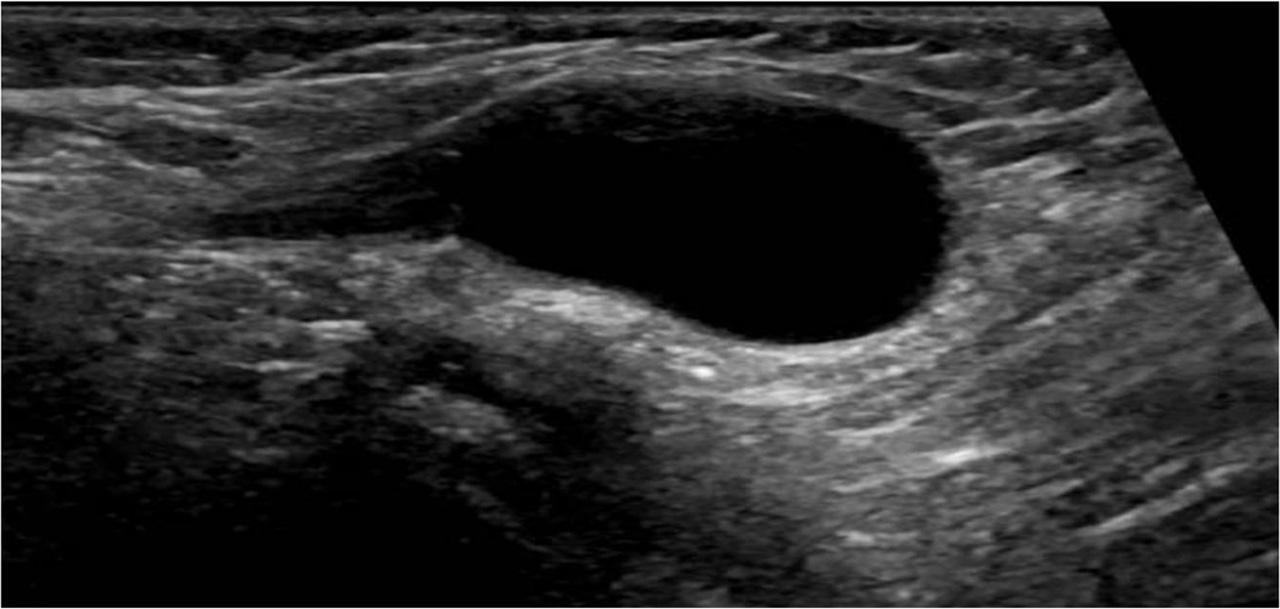

Ultrasound of the right groin was done, revealing a 2 × 1.9 × 1.4 cm fluid-filled superficial cystic lesion seen medial to the pubic bone at the level of the right superficial inguinal canal and 1.1 cm away from the deep inguinal ring (Fig. 1). No abnormal vascularity was depicted on color Doppler images (Fig. 2). The amount of fluid did not change with the Valsalva maneuver. No intervening bowel loops were seen. The left inguinal canal was normal. The rest of the examined abdominal viscera showed no abnormalities. The sonographic features were compatible with a hydrocele of the canal of Nuck. The patient was referred to the pediatric surgical clinic for consultation, where conservative management and observation were recommended, with surgical repair to be considered if any symptoms or complications should occur.

Longitudinal gray-scale superficial ultrasound of the right groin showing an elongated fluid-filled cystic lesion medial to the pubic bone and at the level of the right superficial inguinal ring. No herniation of pelvic organs or bowel loops seen